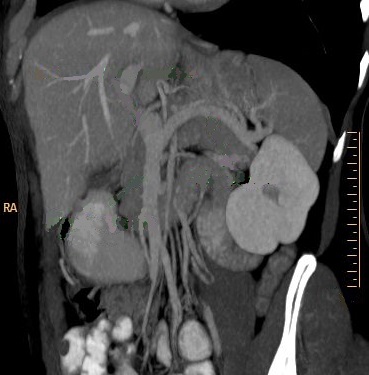

Images de veine splenique , des

veines mesenterique et veine porte apres

recontructionale en 3D de phase veineuse a mode MIP

vue en oblique anterieue droit ( OAD ) . La rate

être en vue tres nette sous diapragmatique gauche .

Image TDM + PDC intra veineuse , temps veineuse |

|

Image de recontructional en

3D a mode MinIP ( Minimun itensity projection ) . se

donne de image de la rate sous phrenique gauche ,

image du pancreas et duodenum |